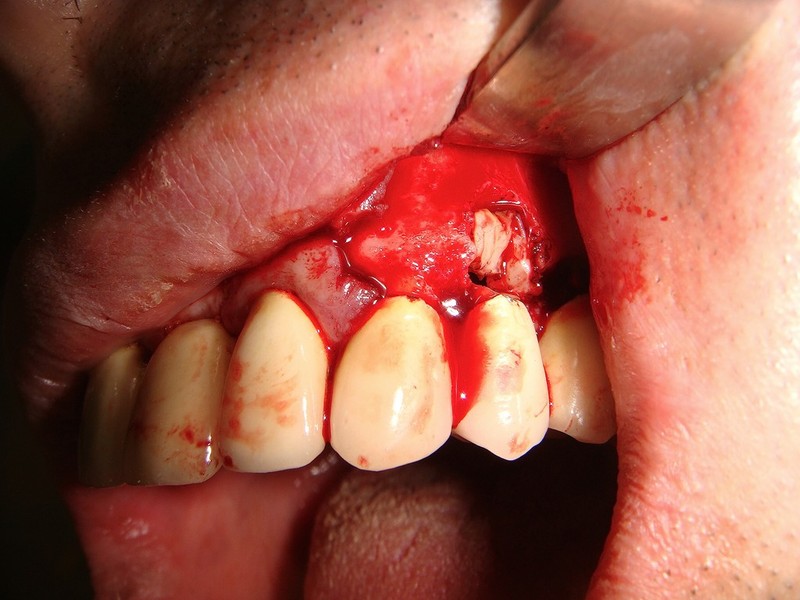

Estrazione radice e inmnesto Epitelio-Connettivale

Estrazione di un canino incluso e contestuale inserimenti di impianto e innesto osso eterologo